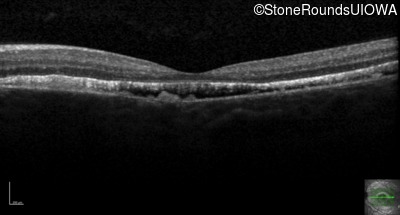

Best Disease (IIB)

Age at visit: 14 years

This 15 year old girl came to medical attention during a routine athletic vision screening when the acuity in her right eye was observed to be abnormal.

Diagnosis & molecular findings

Disease Gene Allele 1 variant(s) Allele 2 variant(s) Inheritance mode

Best Disease BEST1 Asp228Glu GAC>GAG Asn259 ins2aacAA AR